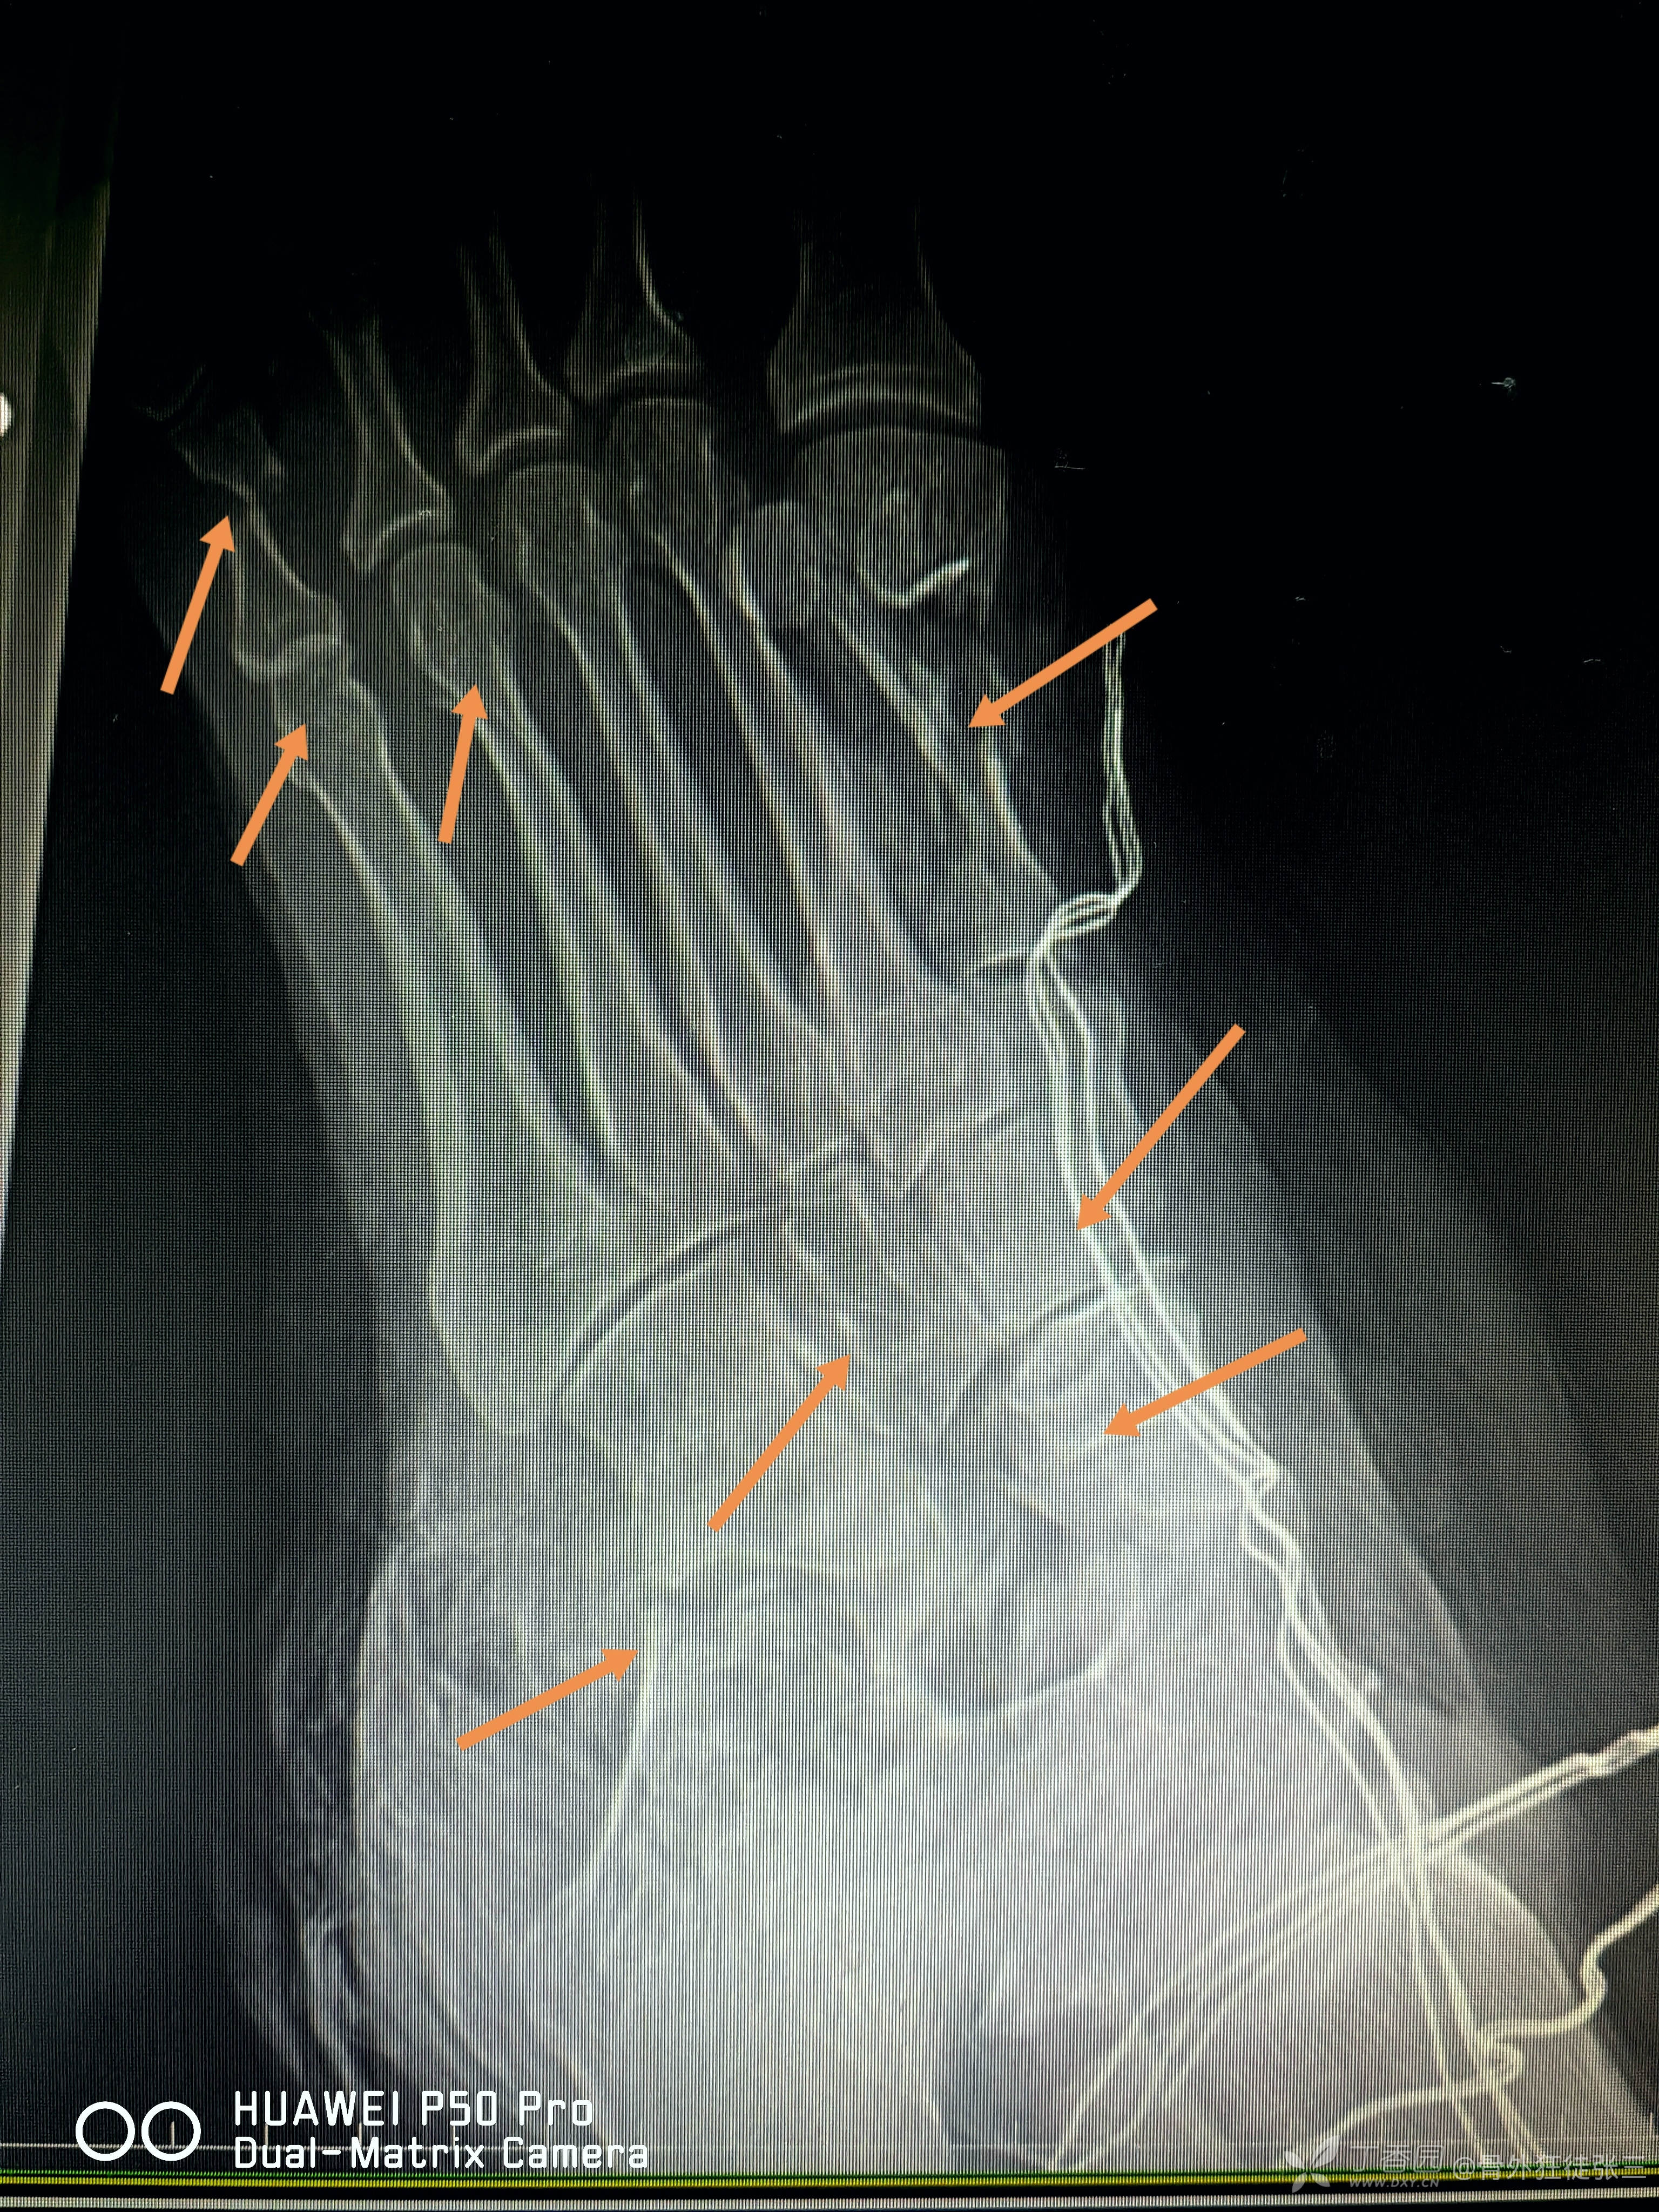

跟骨,距骨,骰骨,楔骨,跖骨1,多发骨折脱位

没有一根针多余

一把钢针